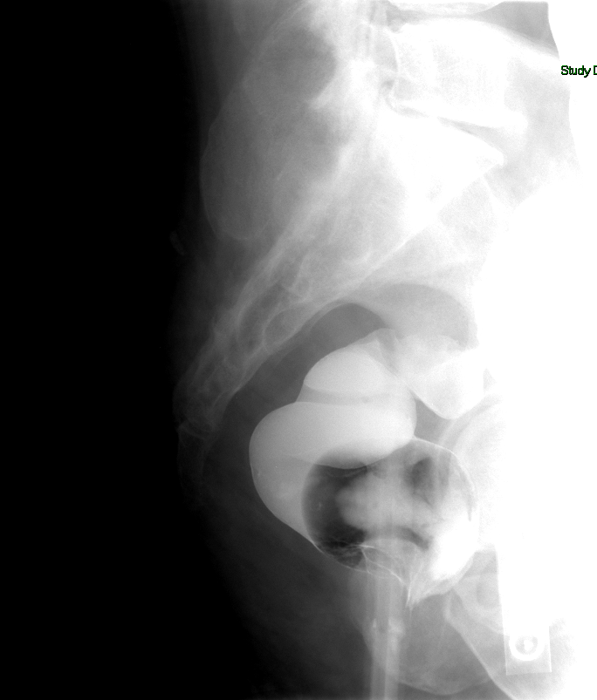

- Continue to slowly instill contrast material until the rectosigmoid has become fully distended with contrast material. Obtain spot images of rectosigmoid colon with the patient in both the right posterior and left posterior obliques

(key image 5).

- Proceed to instill contrast material into the colon until the contrast material has reached the cecum and the colon appears fully distended.

- It may be necessary to move the patient into different positions to facilitate the progression of contrast material

- Intermittently look with the fluoroscope while the contrast material moves through the colon. As areas of the colon become distended with contrast material, obtain spot images

(key image 6)

(key image 7)

(key image 8)

(key image 9).

- Be sure obtain images of the entire contrast material filled colon.

- To obtain optimal images of the splenic flexure, place the patient in an RPO or LAO position

(key image 10).

- To obtain optimal images of the hepatic flexure, place the patient in an LPO or RAO position

(key image 11).